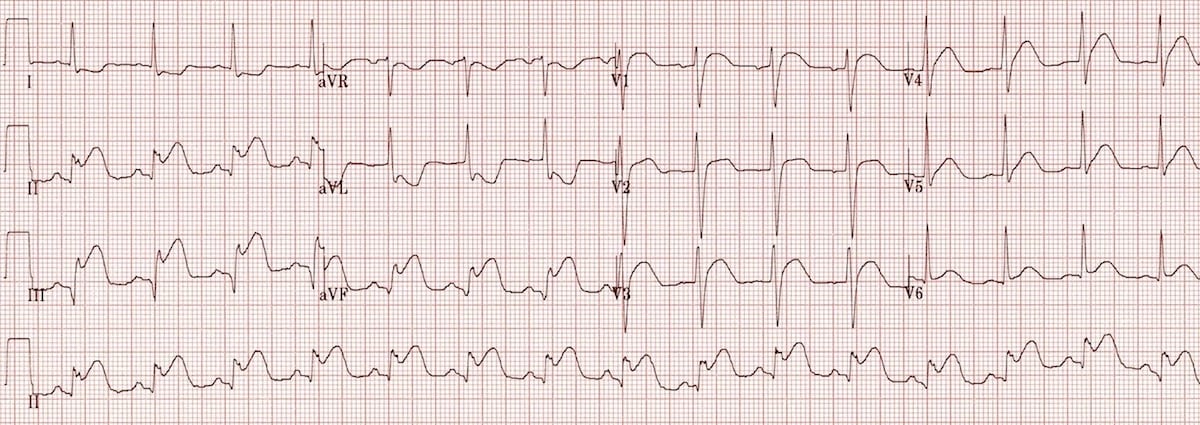

This is an ECG of monomorphic VT. Note the very regular, broad complex tachycardia and the same QRS morphology throughout.

https://litfl.com/ventricular-tachycardia-ecg-library/

© Life in the Fast Lane. Licensed under CC BY-NC 4.0

This is an ECG of polymorphic VT (specifically, Torsades de Pointes – a type of polymorphic VT). The varying QRS morphology can be appreciated, with the characteristic morphology of QRS complexes “twisting” around the isoelectric line.

https://litfl.com/torsades-de-pointes-ecg-library/

© Life in the Fast Lane. Licensed under CC BY-NC 4.0